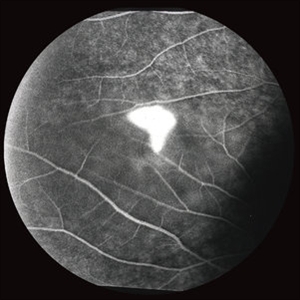

Central Serous Chorioretinopathy with Smokestack FA Early Phase

CSCR with smokestack, FA, early phase.

Condition/keywords: central serous chorioretinopathy (CSCR), FA early phase, smokestack